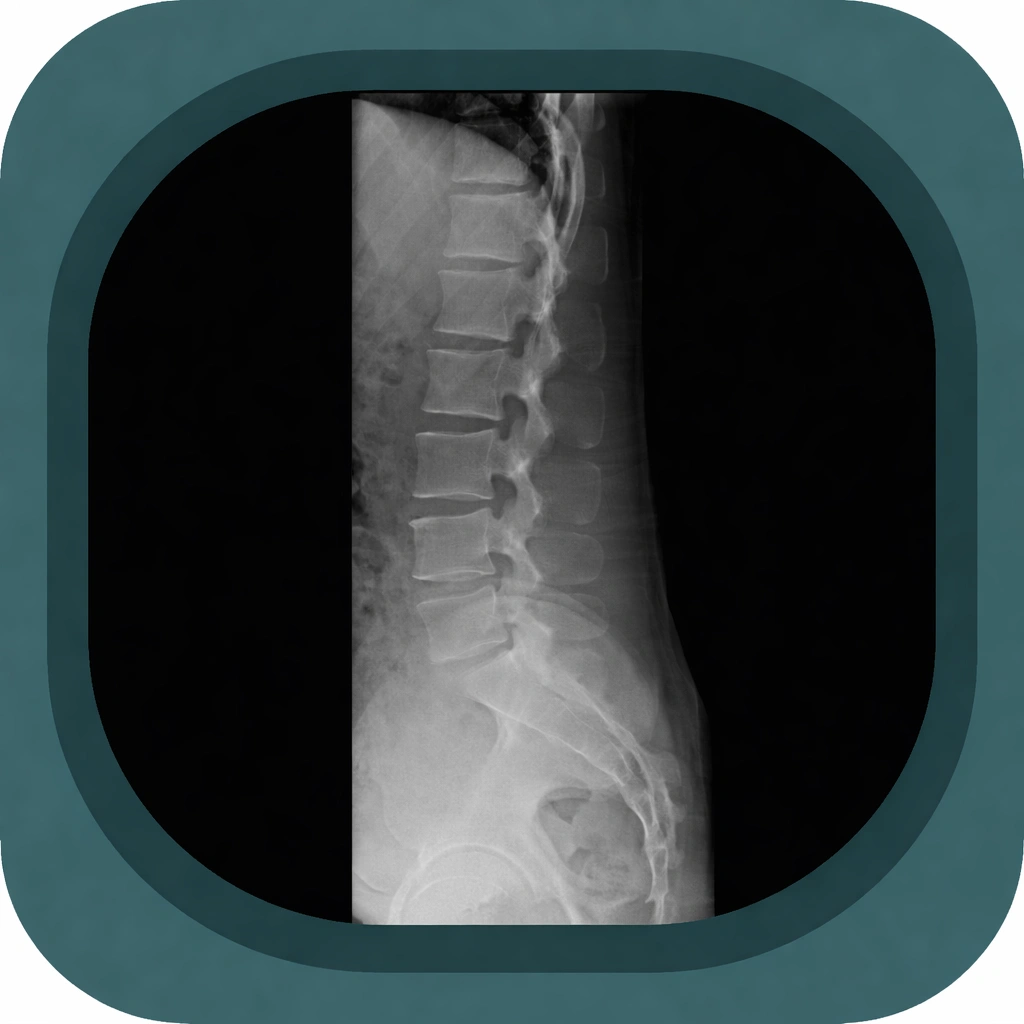

Explore high-quality X-ray anatomy from head to toe. Our database features carefully labelled images to visualize fine structures—perfect for radiologists, students, and surgeons.